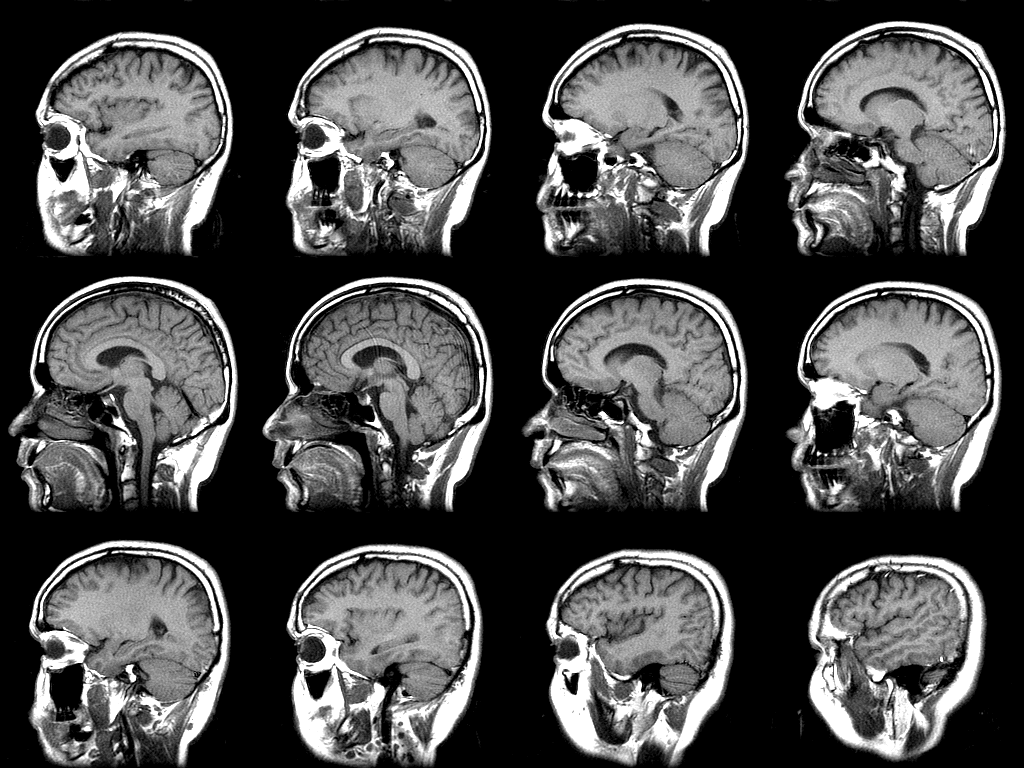

الرنين المغناطيسي للدماغ وأنواع أجهزة الرنين المغناطيسي مجلتك

أشعة الرنين المغناطيسي على المخ مجلتك

التصوير بالرنين المغناطيسي Mri Mayo Clinic مايو كلينك

ماهو الرنين المغناطيسي واستخداماته ماهو الرنين المغناطيسي واستخداماته

استخدامات التصوير بالرنين المغناطيسي